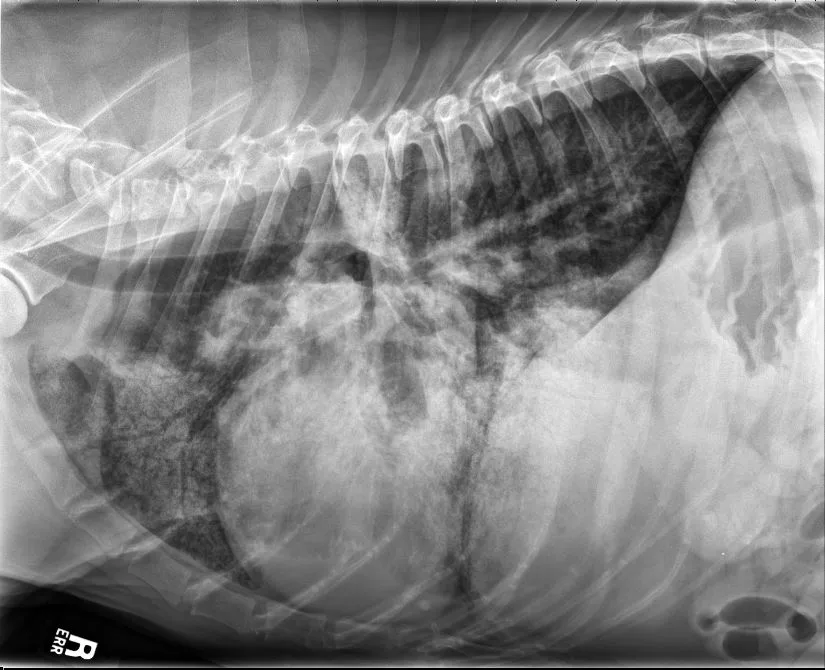

FIGURE 11 Right lateral (left) and VD (right) projections of a crossbreed dog with tricuspid valve dysplasia. The cardiac silhouette has increased width, and the regions of the right atrium and ventricle show roundness. The cardiac apex is displaced to the left secondary to right-sided enlargement (right). The caudal vena cava (arrowheads) is dilated, and there is loss of abdominal serosal detail secondary to increased systemic venous pressures and right-sided CHF, respectively. The pulmonary vasculature is small secondary to pulmonary hypoperfusion (given significant regurgitation across the tricuspid valve and decreased forward blood flow). VHS, VLAS, M-VLAS, and VRHi collected from the right lateral view are 12.3, 2.3, 2.7, and 3.8, respectively. Images courtesy of Bruna Del Nero, DACVIM (Cardiology)